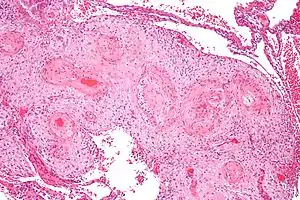

Micrograph showing hypertrophic decidual vasculopathy, the histomorphologic correlate of gestational hypertension. H&E stain.

In pathology, hypertrophic decidual vasculopathy, abbreviated HDV, is the histomorphologic correlate of gestational hypertension, as may be seen in intrauterine growth restriction (IUGR)[1] and HELLP syndrome.

The name of the condition describes its appearance under the microscope; the smooth muscle of the decidual (or maternal) blood vessels is hypertrophic, i.e. the muscle part of the blood vessels feeding the placenta is larger due to cellular enlargement.

The morphologic features of mild and moderate HDV include:[1]

- Perivascular inflammatory cells,

- +/-Vascular thrombosis,

- Smooth muscle hypertrophy, and

- Endothelial hyperplasia.

Severe HDV is characterized by:

- Atherosis - foamy macrophages within vascular wall, and

- Fibrinoid necrosis of vessel wall (amorphous eosinophilic vessel wall).